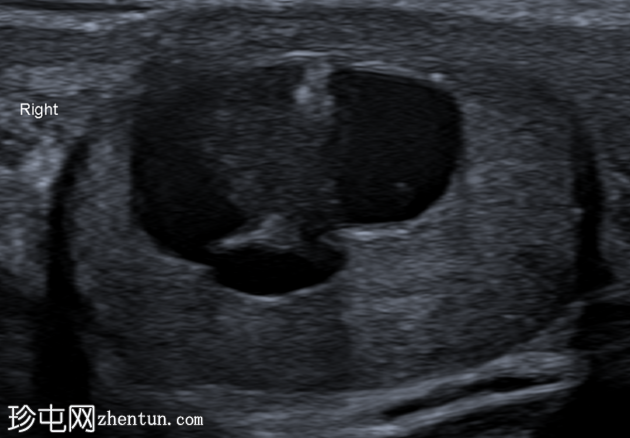

纵切面

右侧睾丸内可见一异质性肿块,大小约10 x 14 x 15 mm,包含实性和囊性成分。肿块内可见多发小钙化灶。彩色多普勒超声检查显示肿块内血流信号较少。